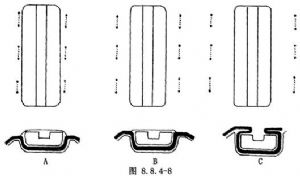

一般採用褥式縫合或X字形縫合。縫線的跨度可根據裂孔大小、所需外加壓物的大小以及需要形成的鞏膜嵴高度等決定。最好在預置縫線前先選好要用的加壓物,這樣便可按照所選的加壓物和裂孔位置縫線。跨度大,則形成的鞏膜嵴高。採用硬質硅膠(solid silicon)形成的鞏膜嵴高度與縫線跨度的關係如圖8.8.4-8。一般跨度比加壓物寬度寬2mm,形成較矮的鞏膜嵴;寬3~4mm,可形成較高的嵴。縫線跨度過大,鞏膜發生皺褶。

最後結紮縫線時的鬆緊也影響鞏膜嵴的高度,結紮緊時鞏膜嵴多高些。